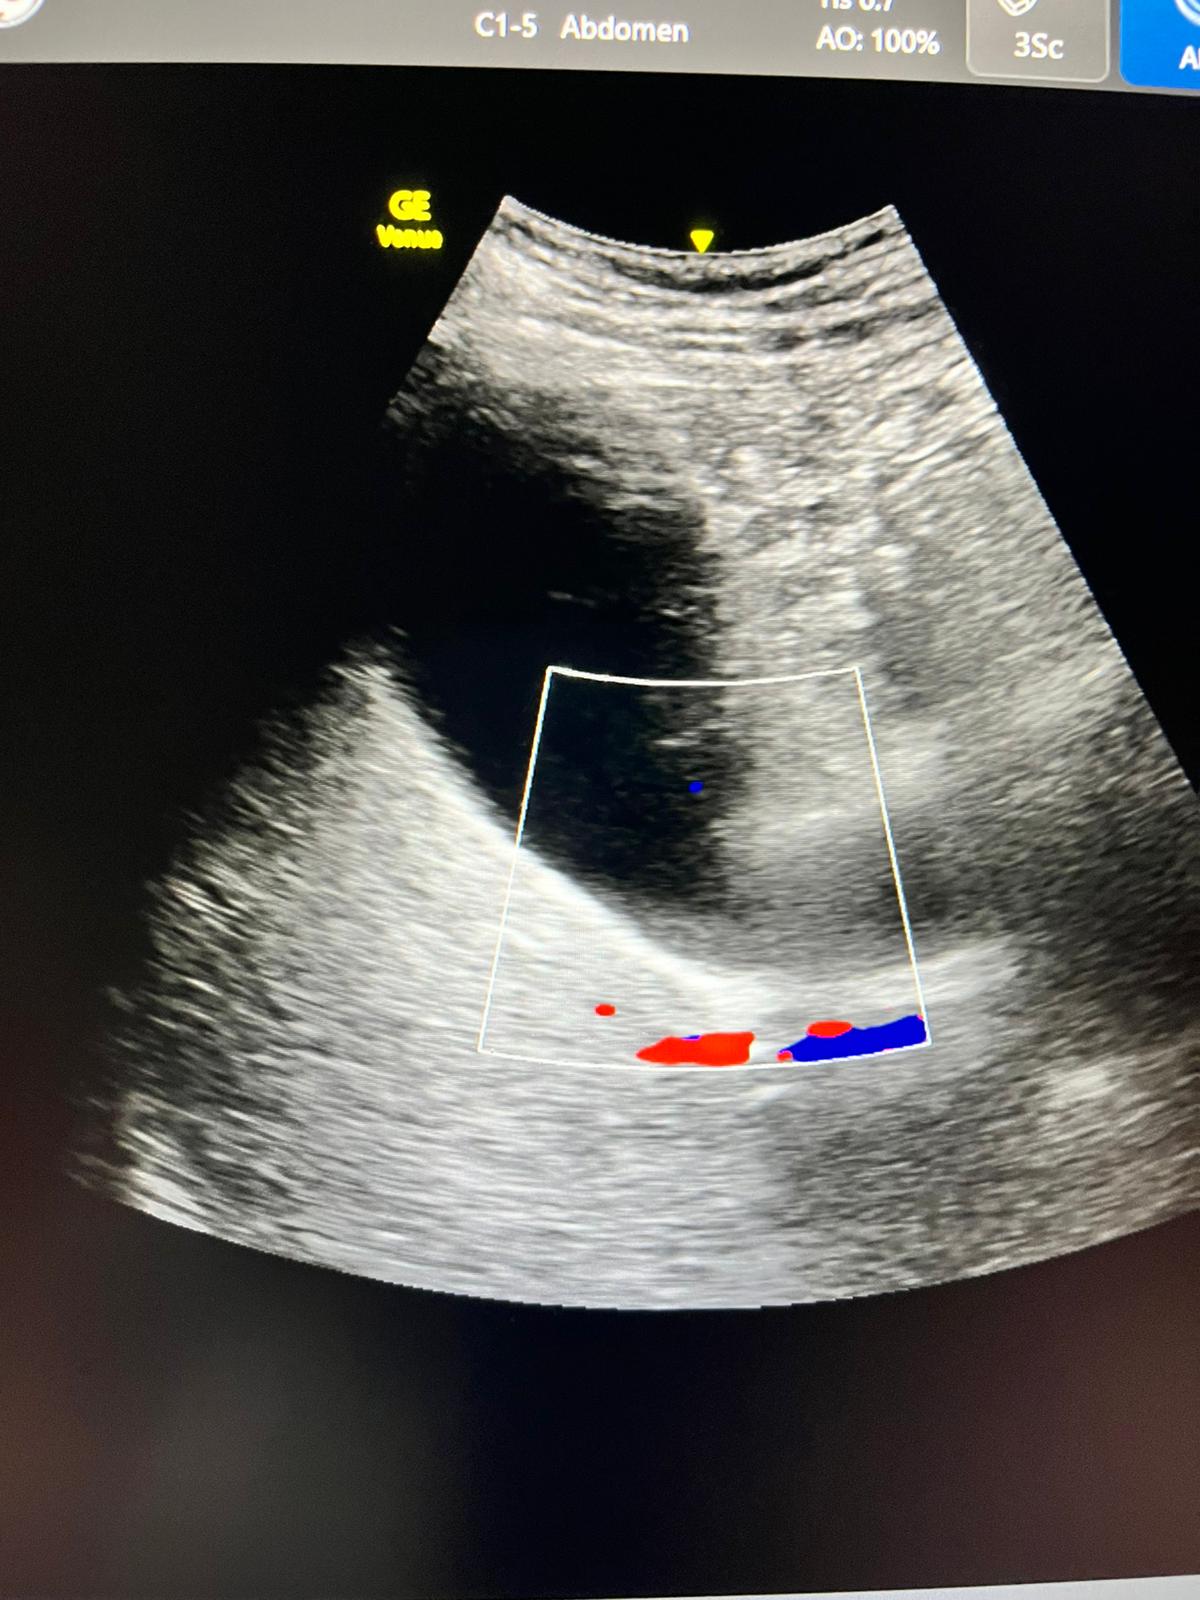

Ecografía: hígado y vías biliares normales sin formaciones expansivas. Coledoco de calibre normal.

Vesícula biliar distendida con litiasis múltiple suncentimétricas y barro biliar de paredes finas.

JC: coledocolitiasis DxD: IAM, cólico biliar.